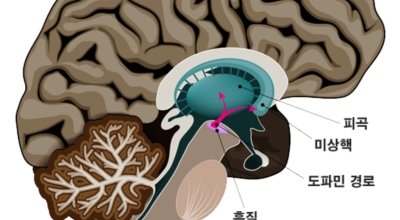

파킨슨병은 도파민 분비 신경 세포의 소실로 발생하는 질환으로 알려져 있는데요 도파민이란 뇌의 신경세포에서 만들어지는 물질로 세포와 세포 간의 신호를 전달하는데 이용되는 신경 전달 물질 중 한가지로 이 도파민이 감소함에 따라 파킨슨병이 걸린다고 하는데 이 도파민 세포가 떨어지는 이유는 아직 정확히 밝혀지지 않았다고 합니다.